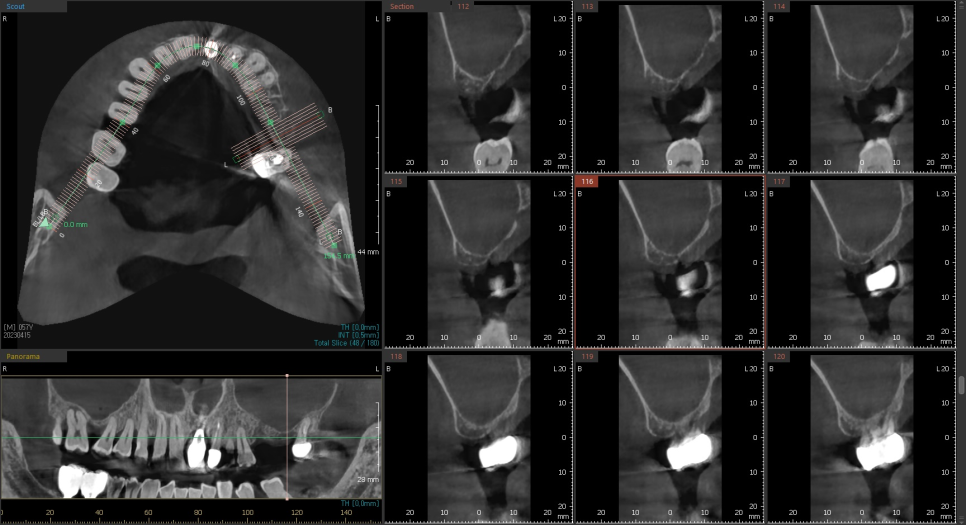

23.05.20

상악동 거상술을 동반한

상일동 임플란트 완료 사진입니다.

뼈가 월드컵 경기장 모양처럼

돔 형태로 이식이 된 게 확인됩니다.

수술 전후 차이 한 장으로 보여드릴게요~

뼈가 이식된 것이 보이시죠?

상악동 거상술 수술이 잘 되었습니다.

4개월 뒤의 기다림이 지나고..

임플란트가 뼈와 잘 붙었는지

검사해 주는 기계를 사용하여 확인하였습니다.

(바르디 치과는 어떤 치료이든

정확한 디지털 기계를 사용해 확인합니다.)

이제 완성해도 되겠네요.